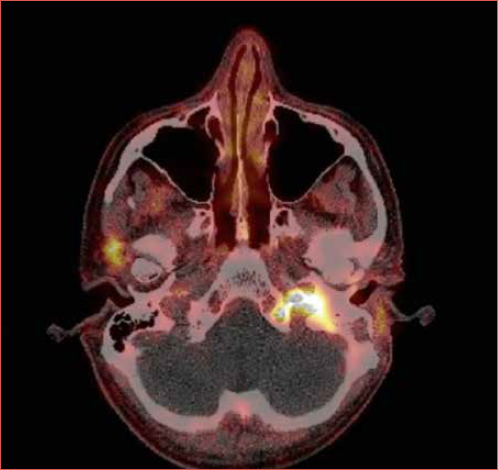

Six months after the last ear surgery, the patient presented with ipsilesional glossopharyngeal and hypoglossal nerve palsy. MR imaging and 68Ga-DOTATATE-PET/CT revealed an avid mass in the jugular foramen, extending into the hypoglossal, carotid and vertebral canal of C1 (Cover figure). Because the tumour was deemed unresectable, the patient was treated with local radiotherapy (68 Gy total dose) and somatostatin analogue (SSA) therapy every 4 weeks. Six months later, 68 Ga-DOTATATE-PET scanning showed stable local disease and no metastases.

Figure 1. CT and MR imaging of the middle ear neuroendocrine tumours of patient 1 (A and B) and patient 2 (C and D). A) Axial T1-weighed MRI scan, demonstrating the primary tumour as a mass in the left mastoid with extension to the temporal fossa and preauricular region; B) Axial temporal bone CT, showing soft tissue in the left middle ear cavity with suspicion of erosion of the malleus and anterior temporal bone; C) Axial T1-weighed MRI scan, demonstrating the recurrent right middle ear mass at the level of the cochlea; D) Axial temporal bone CT, showing soft tissue completely filling in the right middle ear cavity.